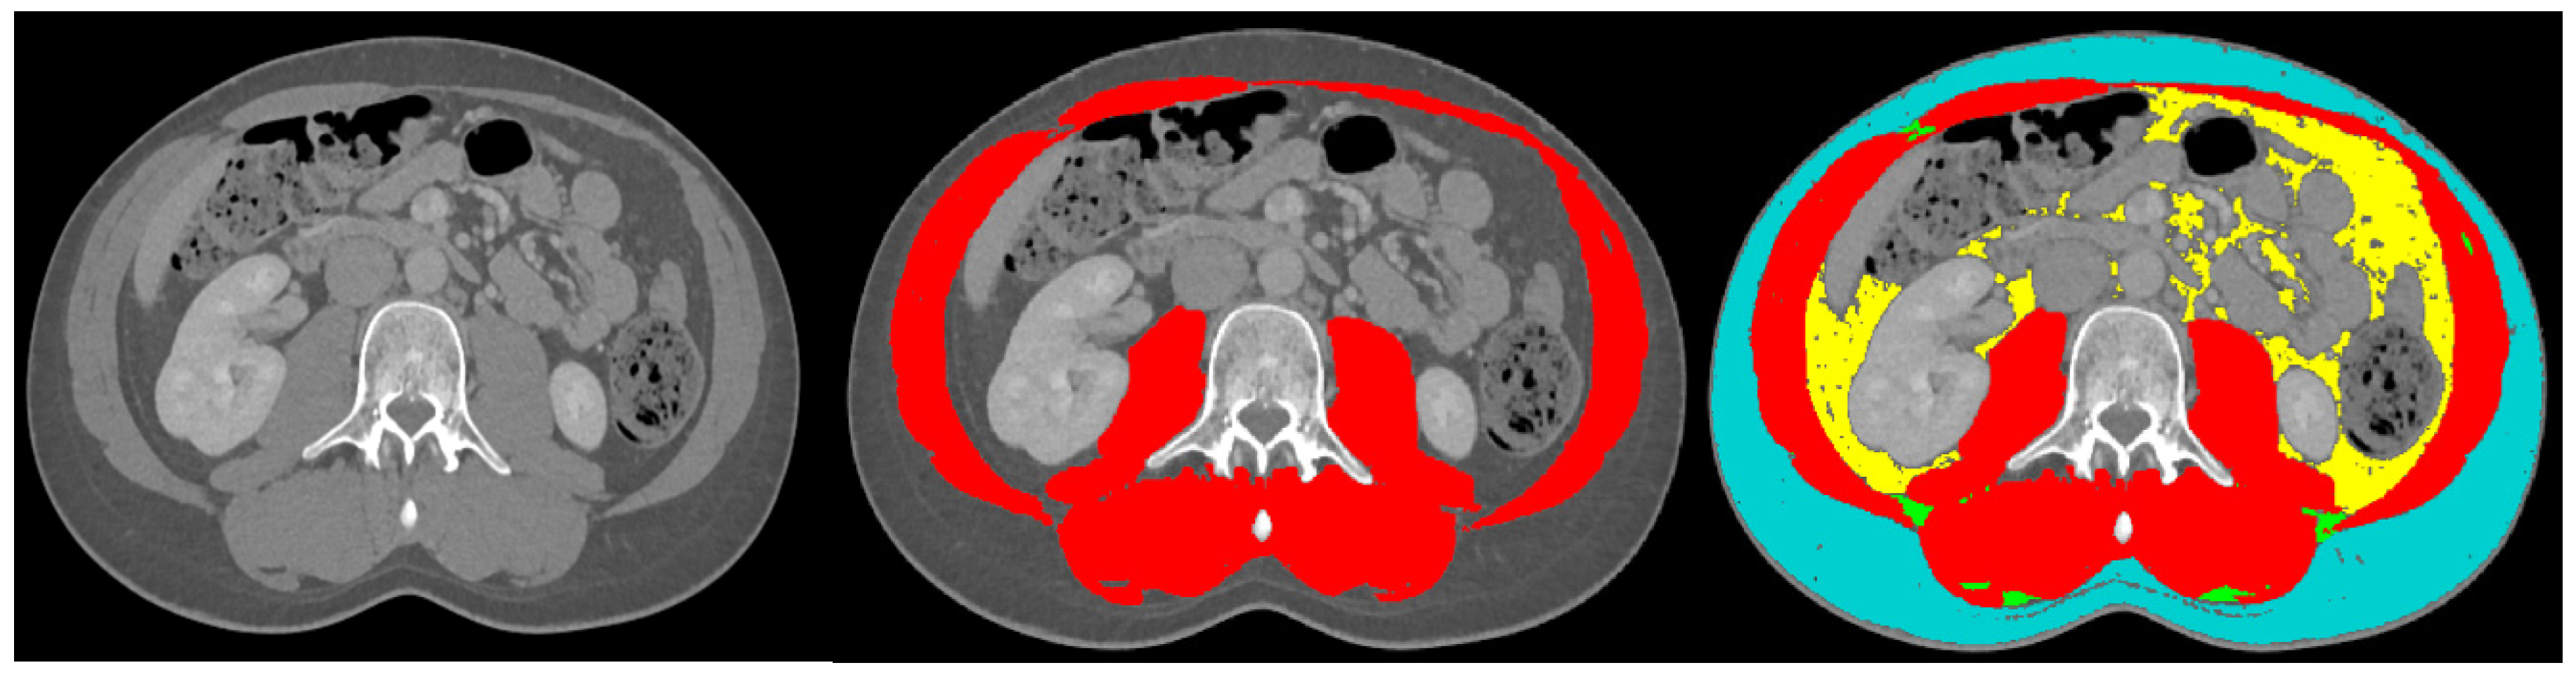

The following data were collected: baseline demographic characteristics, height, weight and BMI. The WHO 2019 classification was used for the histological confirmation of grading and staging of the GEP-NET []. There are 4 categories of weight based on BMI: <18.50 kg/m2 is underweight, 18.51–24.99 kg/m2 is normal weight, 25.00–29.99 kg/m2 is overweight and >30 kg/m2 is obese []. Primary tumours were categorised as located in the small intestine (including duodenum), pancreas or other. For staging, the Tumor Node Metastasis (TNM) system was used, originating from the Union for International Cancer Control (UICC), 8th edition (2016). The American Society of Anaesthesiologists Classification (ASA) was used for vitality []. Surgical procedures were categorised to the small intestine (including all surgery to the colon), pancreas and other. The Clavien–Dindo classification for surgical complications was used [], and a score of ≥3 was considered as a major surgical complication and considered as clinically relevant. Surgical complications were categorised into infectious (chest infection/pneumonia, skin infection, urinary tract infection, abscess), ileus (including gastropareses), anastomosis-related (leakage, stenosis) and other. Surgical complications within 30 days following surgery were included. For body composition analysis, a CT scan suggesting the presence of a NET was analysed using a single slice at lumbar level L3. Previous research has suggested that this area corresponds well with entire body muscle and fat mass [,]. The body composition analyses were performed using Slice-O-Matic software (5.0 Rev-8, Tomovision, Milletta, Magog, QC, Canada). The muscle and fat areas were identified and marked with a colour-coded label. These colour-coded labels were based on Hounsfield units (HU) for muscle, −29 HU to +150 HU; for subcutaneous adipose tissue, −150 HU to −50 HU; and for visceral adipose tissue, −190 HU to −30 HU. Figure 1 provides an example of body composition analysis. Sarcopenia was present if the skeletal muscle index was <53 cm2/m2 if BMI > 25 kg2/m2 or <43 cm2/m2 if BMI < 25 kg2/m2 for males and <41 cm2/m2 for females [,]. Myosteatosis was present if the muscle attenuation was <33 HU if BMI > 25 or <41 if BMI < 25 for both males and females []. The subcutaneous and visceral adipose tissue areas were added together to obtain the total adipose tissue area (TAT); adipopenia was present if males had TAT < 364 cm2 and females had TAT < 318 cm2 [].

Figure 1.

Example body composition analysis. The left image displays a cross-sectional view at the lumbar level L3, the middle image indicates muscle mass tagged in red, and the right image shows subcutaneous adipose tissue tagged in blue and visceral adipose tissue tagged in yellow.